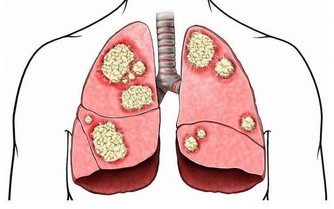

近些年來,黑色素瘤的發病率增長得很快,而且轉移率高,治療難度大,預後差,因此黑色素瘤也被稱為“癌中之王”,如果能在早期就將其解決,治療成功的希望很大。

手術治療。大部分的早期黑色素瘤能通過外科手術治療治愈,如果是Ⅰ-Ⅱ期的患者,一般是原發灶手術切除,Ⅲ期患者除了原發灶手術切除,還要做區域淋巴結清掃術,Ⅳ期孤立轉移的患者一般也推薦手術治療。

Ⅰ-Ⅱ期患者治療後5年生存率為98%,中晚期患者的預後效果就不太理想了,分期越高,治療難度越大,預後效果越差,而大部分患者發現時即是中晚期。因此,也提醒大家

免疫治療。免疫治療的出現給黑色素瘤患者的生存期帶來了極大的改善,黑色素瘤患者在十年前普遍生存期不到一年,不到十年的時間裡,由於免疫治療的發展,黑色素瘤逐漸有希望成為一種慢性病,黑色素瘤患者的5年生存期已經上升到50%左右。